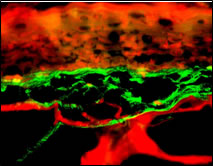

Abb. 4: Immunfluoreszenz-Darstellung der Elastine in normaler menschlicher Haut und im Ganzhautmodell

Elastin in normaler menschlicher Haut (oben) und im Hautequivalent (unten, 250fache Vergößerung). Immunfluoreszenzstudie an gefrorenen Hautschnitten nach 14 Tagen Kultivierung an Air-Liquid Interface.

In dem hier verwendeten Hautmodell exprimieren die Fibroblasten auch Elastin (Abb. 4). Der Einfluss verschiedener Wirkstoffe auf Elastinmenge und Ausrichtung der Elastinfasern ist Gegenstand der aktuellen Forschung.